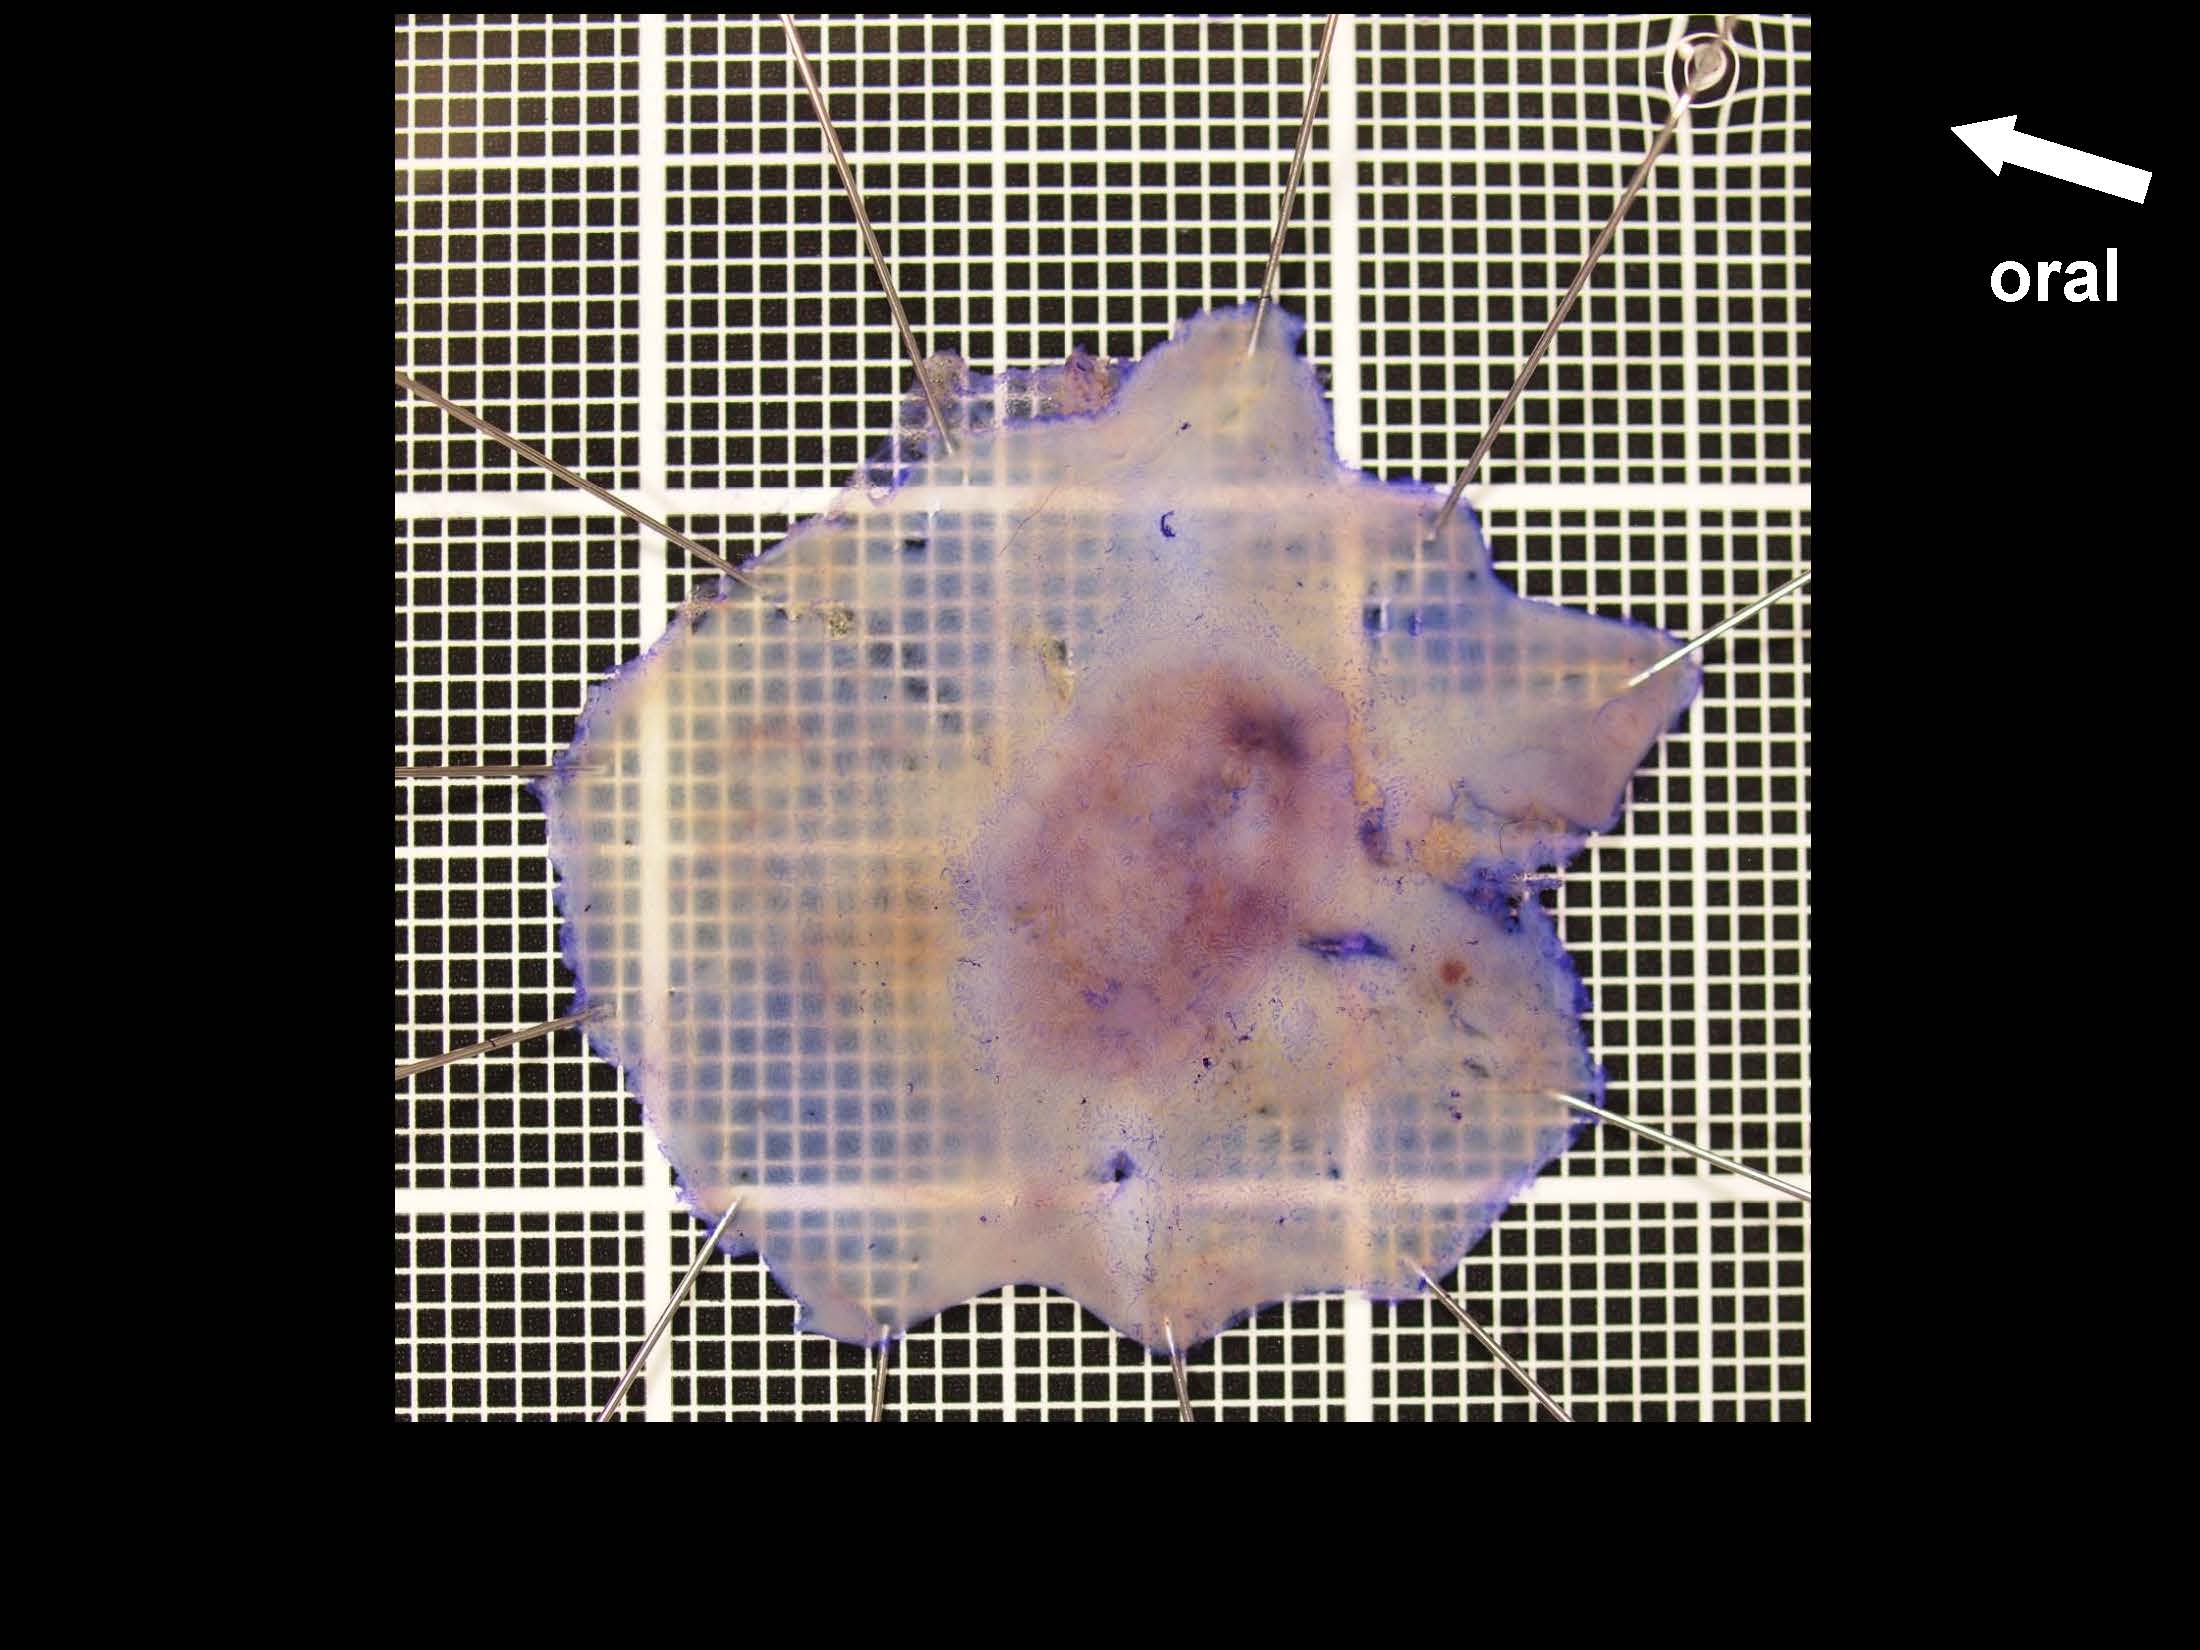

消化管Mapping~大腸~ 2021.10.27

消化管Mapping~大腸~

消化管Mapping

全ページPDFのダウンロードはこちら